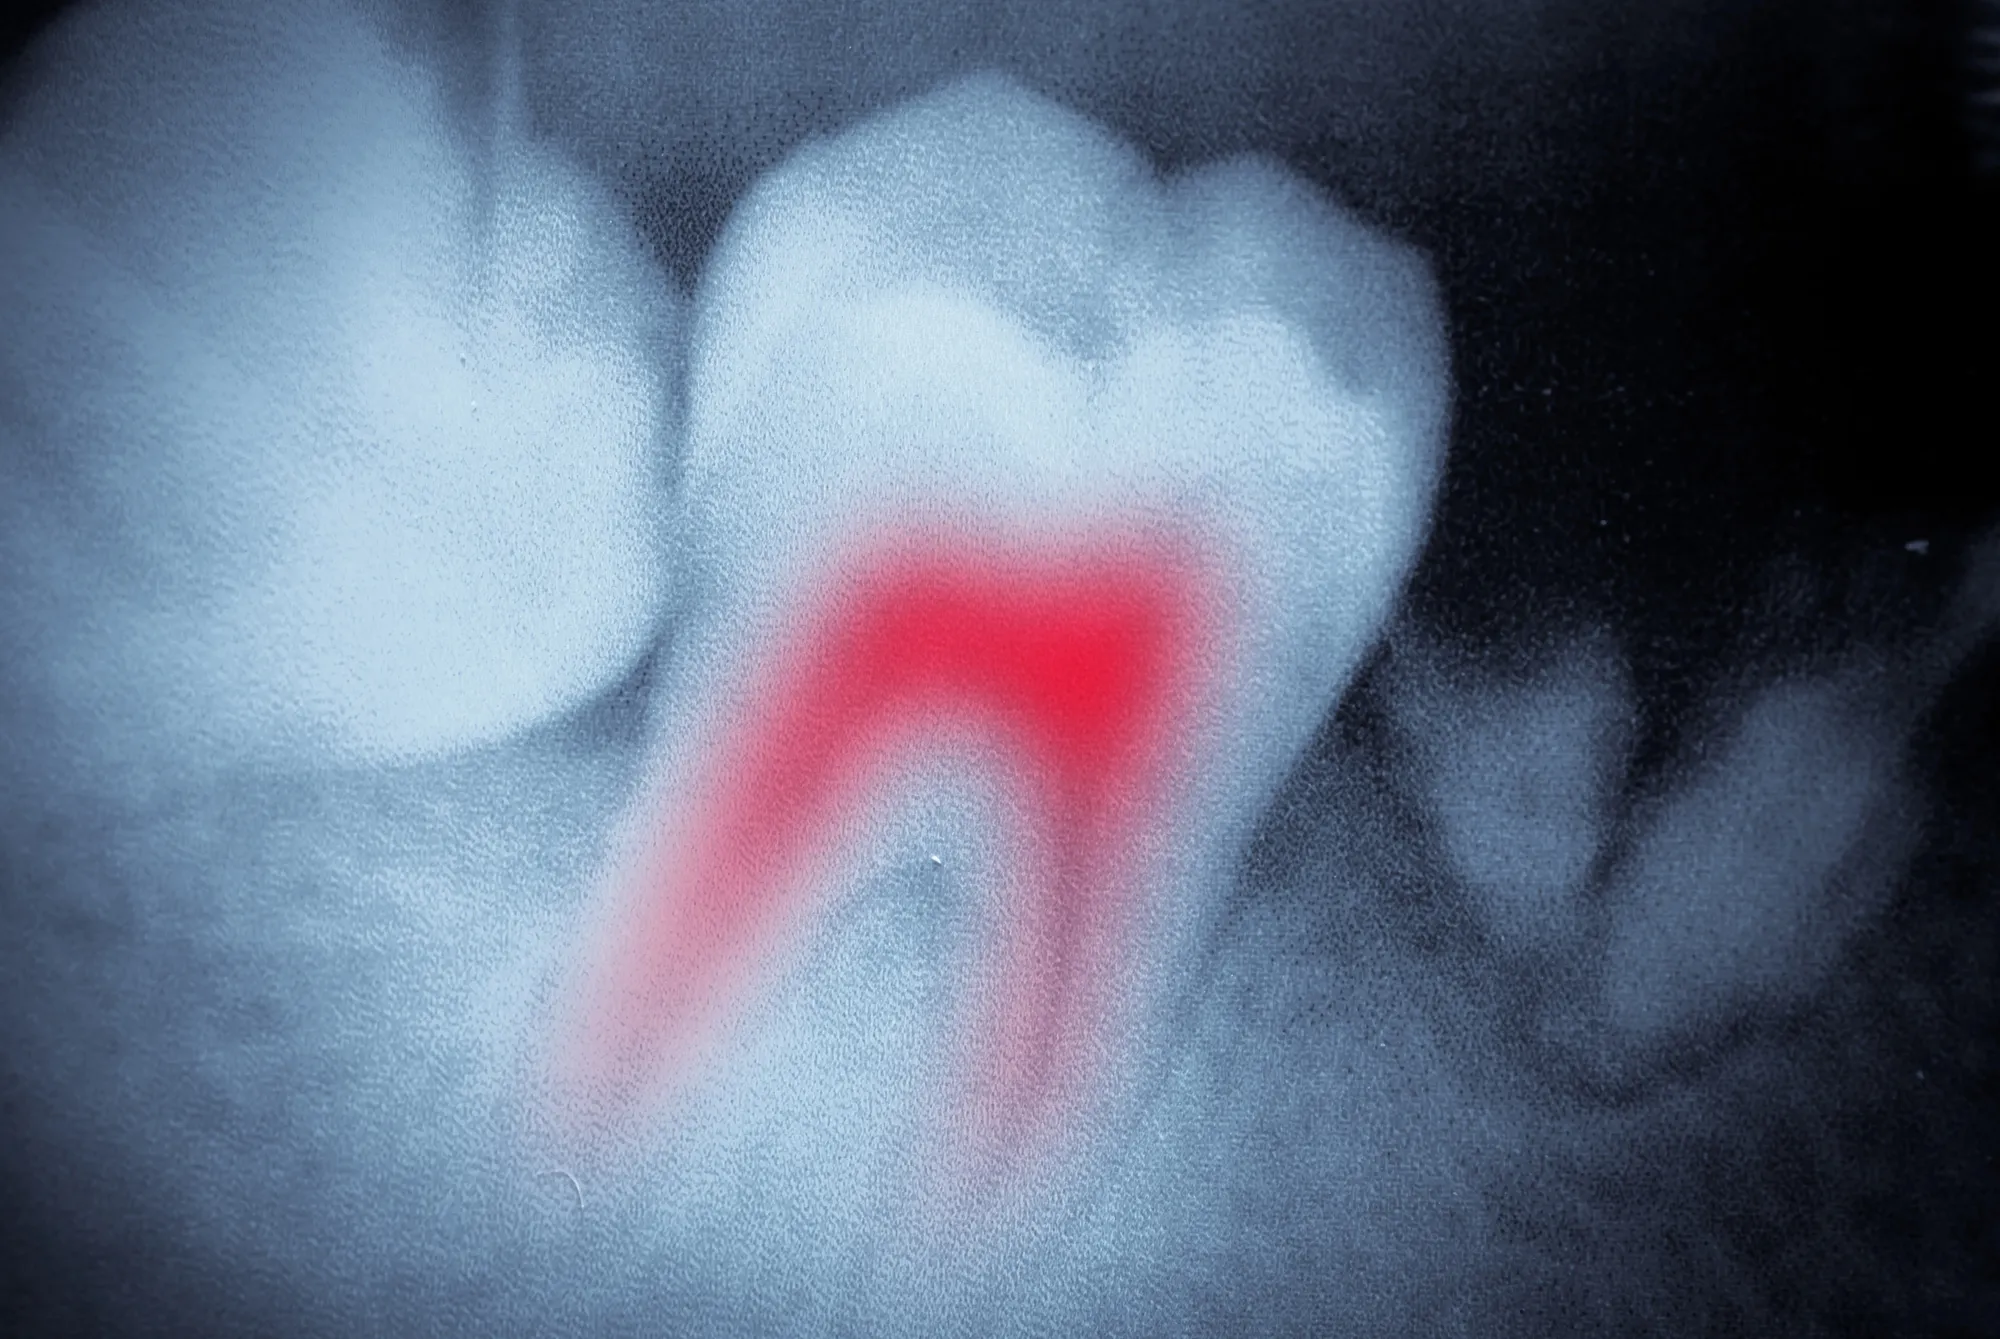

Why Is Root Canal Therapy Necessary?

You might need a root canal if your tooth has:

- Deep decay reaching the pulp

- Cracks or chips exposing the nerve

- Severe tooth pain or sensitivity to hot and cold

- Swelling or infection at the tooth root

Treating these issues promptly prevents more extensive procedures, including tooth removal. In most cases, saving the natural tooth is the better long-term choice.